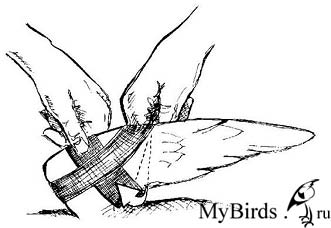

Консервативная фиксация с помощью крестообразной повязки. Photo: C. Haupt

Консервативная фиксация должна проводиться только на одной стороне, и используемый для повязки материал не должен повредить перья. Наиболее подходящими являются самоклеящиеся повязки. Неповрежденное оперение для птицы столь же жизненно важно, как и целостный скелет. Свою эффективность доказала крестообразная повязка (см. рисунки). После удаления повязки птицу необходимо несколько дней тренировать, чтобы укрепить ее мышцы. С этой целью ее можно заставлять каждый день карабкаться вверх с одновременным взмахиванием крыльев или поощрять ее упражняться на полу. Не рекомендуется разрешать птице летать в помещении, т.к. стрижи развивают высокую скорость за короткое расстояние, и птица может легко причинить себе вред.

Крыло расположено в физиологическом положении. Чувствительную к давлению растянутую кожу крыла (показано стрелкой) необходимо осторожно удерживать в пальцах. Рисунок: C. Haupt

Эластичная повязка накладывается снизу вверх вокруг плечевой кости, затем через плечевой сустав и вокруг запястья. Рисунок: C. Haupt

Повязка располагается дорсально через крыло, снова перетягивается крестообразно снизу и вдоль под плечевой костью. Рисунок: C. Haupt